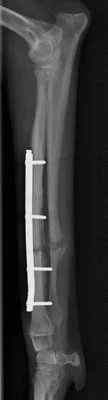

イタリアン・グレーハウンドの両前肢骨折

右前肢

右前肢はLag Screw固定の併用が可能だったので1期癒合

右前肢は骨片間圧迫を加えているため、骨折端同士が直接癒合します。

そのため仮骨形成が少なく、早期に癒合します。

術後19日 右前肢は治療終了です。